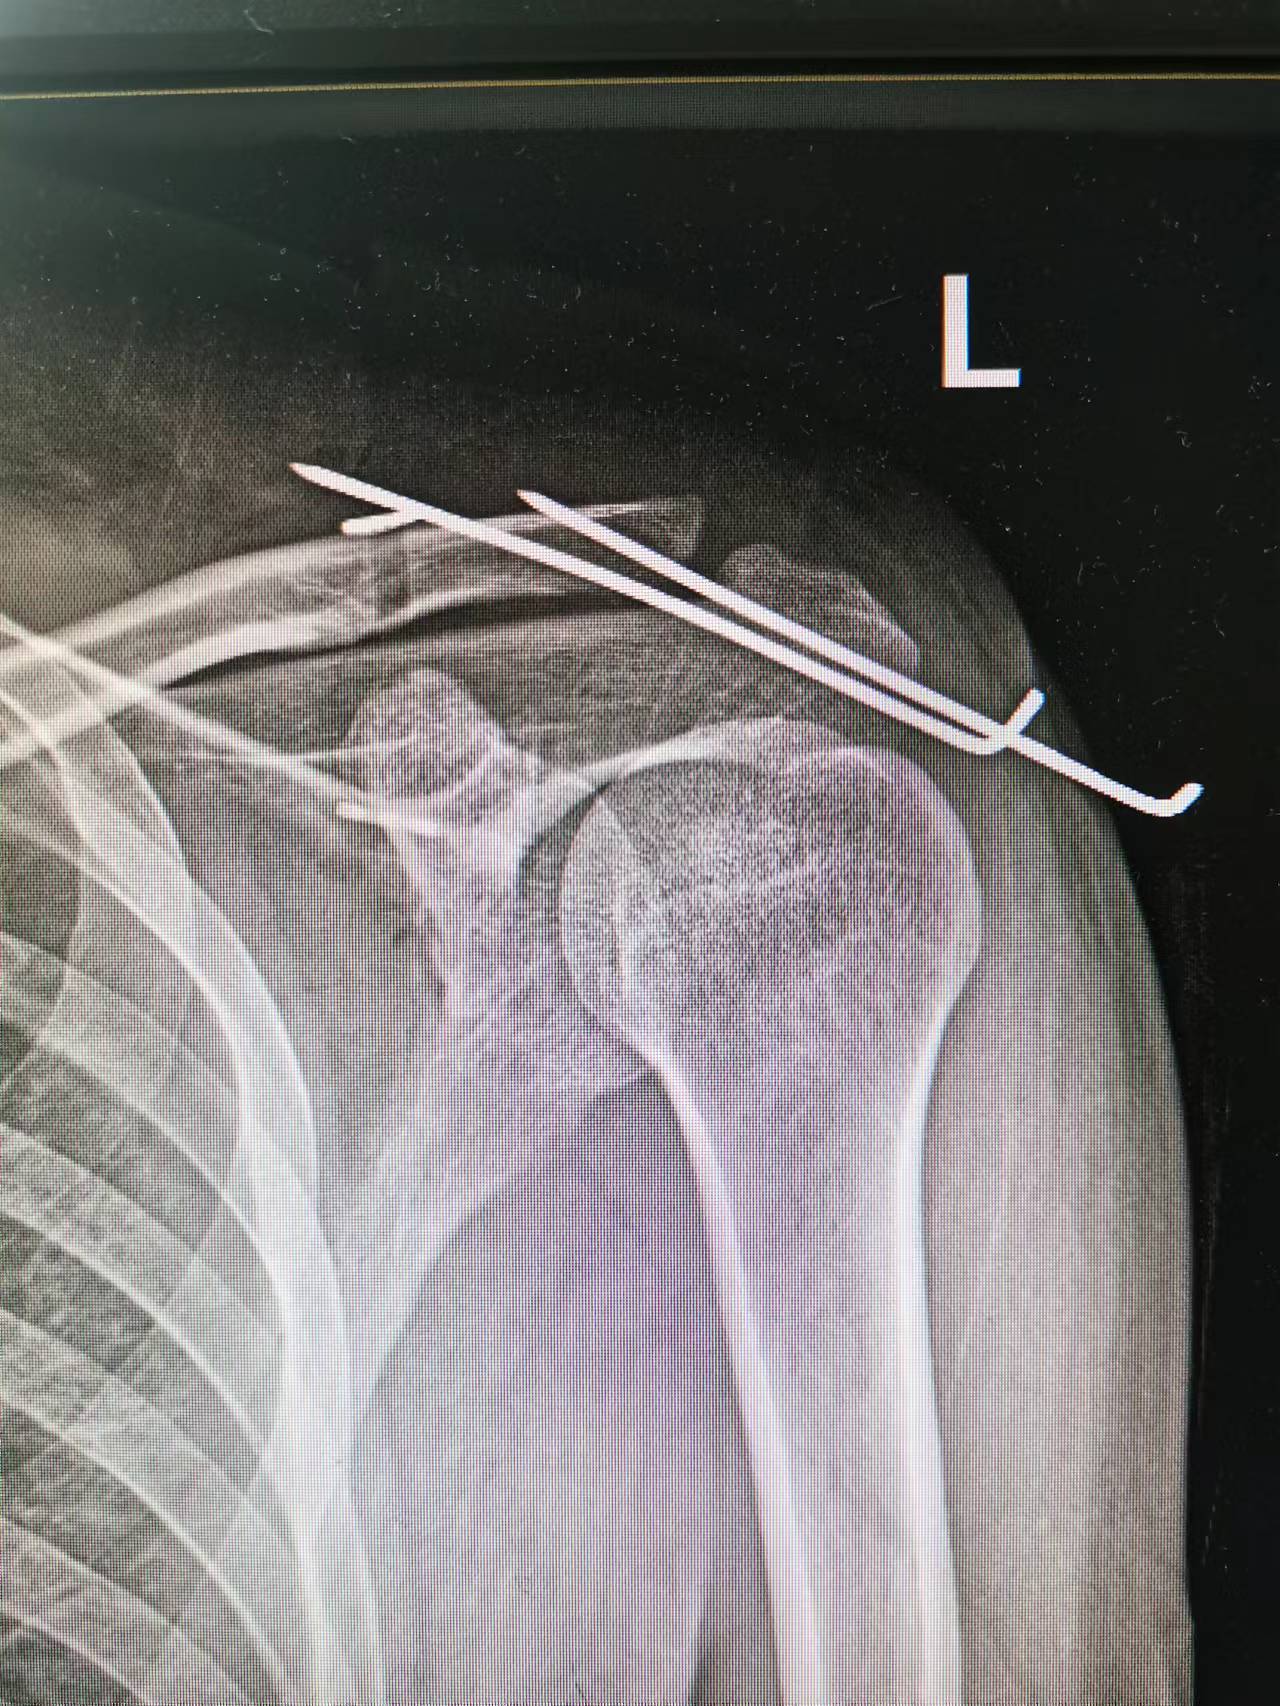

曾女士肩锁关节脱位,为急性损伤,复位较易。而郭先生伤后曾经找过医生为其按摩,复位后就没再管,三周之后有不适来院检查发现仍旧脱位。骨伤科团队分析两个人的损伤情况,对曾女士行肩锁关节脱位切开复位+纽扣钢板固定韧带重建术。而由于郭先生受伤之后时间太久才来进行正规治疗,周围组织有粘连,复位较困难,在应用纽扣钢板固定韧带重建的同时,为防止肩锁关节复位后发生再移位,后在关节部位打入两根钢针,进一步加强固定效果。术后,两人都恢复良好。骨伤团队又为两位患者分别开具院内制剂愈伤胶囊促进恢复。同时在保护伤口创面同时,在周围给予中药贴敷治疗,中药贴敷药物均是骨伤科自行研制,可起到消肿止痛、活血化瘀的功效,同时促进伤口愈合。愈伤胶囊为该院院内制剂,对于骨与软组织急性损伤有良好治疗效果。 |